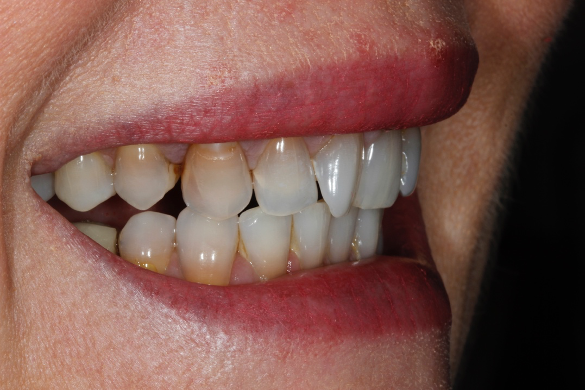

If all of these considerations are taken into account with this case, we can see that the upper right central incisor would be subject to significant tooth reduction (Figures 1b and 1c) and the risk of iatrogenic pulpal death would be increased. Even with immediate dentine sealing and other protective practices adopted.

So, prior to a hygiene work up, the patient was then assessed from an orthodontic perspective for short-term pre-restorative orthodontics. This was to improve tooth position (Figures 2 a,b and c) and allow for a less destructive tooth preparation.